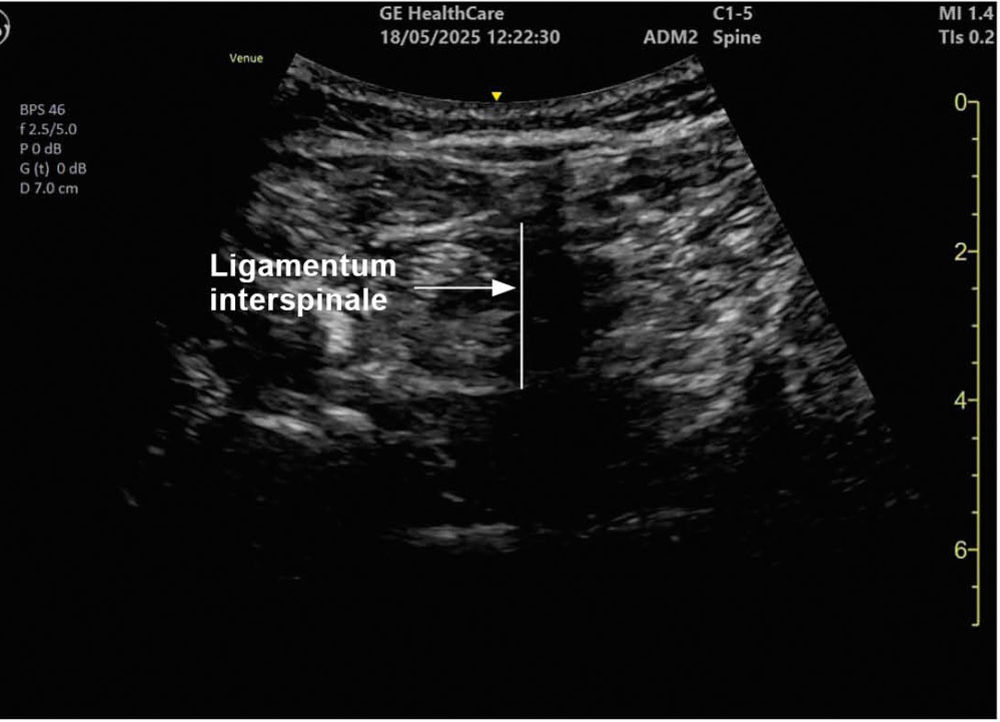

Ein 78-jähriger Patient mit Adipositas permagna (BMI 42) und Coxarthrose wird zur Hüft-Totalendoprothese in Spinalanästhesie geplant. Nach mehreren Fehlpunktionen im Rahmen der klassischen „blinden“ Landmarkentechnik durch die erfahrene Kollegin erfolgt durch einen kurzen Planungs-Ultraschallscan die exakte Charakterisierung des Zwischenwirbelraumes L3/L4 (Lokalisation, Größe und Winkel der Dornfortsätze), eine weitere Punktion gelingt im ersten Versuch (Abbildungen 4 und 5).

Abbildung 4: Sagittalschnitt mit Konvexschallkopf in Höhe L3/L4

Abbildung 5: Transversalschnitt auf Höhe L3/L4

Die Verwendung sonografischer Techniken erlaubt im Lumbalbereich die exakte Darstellung von Dornfortsätzen, Ligamentstrukturen und Epiduralraum. Dies ist insbesondere bei Patienten mit schwierigen anatomischen Verhältnissen relevant. Ein Review durch Perlas und Mitarbeiter ergab, dass die vorherige anatomische Orientierung mit Ultraschall die „First-Pass-Erfolgsrate“ rückenmarksnaher Verfahren deutlich erhöht und gleichzeitig die Inzidenz von Gefäß- und Nervenschädigungen reduziert [12]. Im Rahmen der Spinalanästhesie verbesserte die Verwendung des Ultraschalls Sicherheit und Effektivität der Punktion.

Technik

Der Ultraschall dient im Rahmen rückenmarksnaher Verfahren vor allem der präprozeduralen Planung der Punktion. Nach einer Kombination aus longitudinalen und transversalen Scans zur Identifizierung des „besten“ Zwischenwirbelraumes sowie zur Abschätzung des erforderlichen Punktionswinkels und der plausiblen Zieltiefe [13] erfolgt die Punktion in konventioneller Technik. Bei Unsicherheit kann der Ultraschall zudem zur Bestätigung der korrekten Nadellage, zum Beispiel vor einer Periduralkathetereinlage, eingesetzt werden [14].